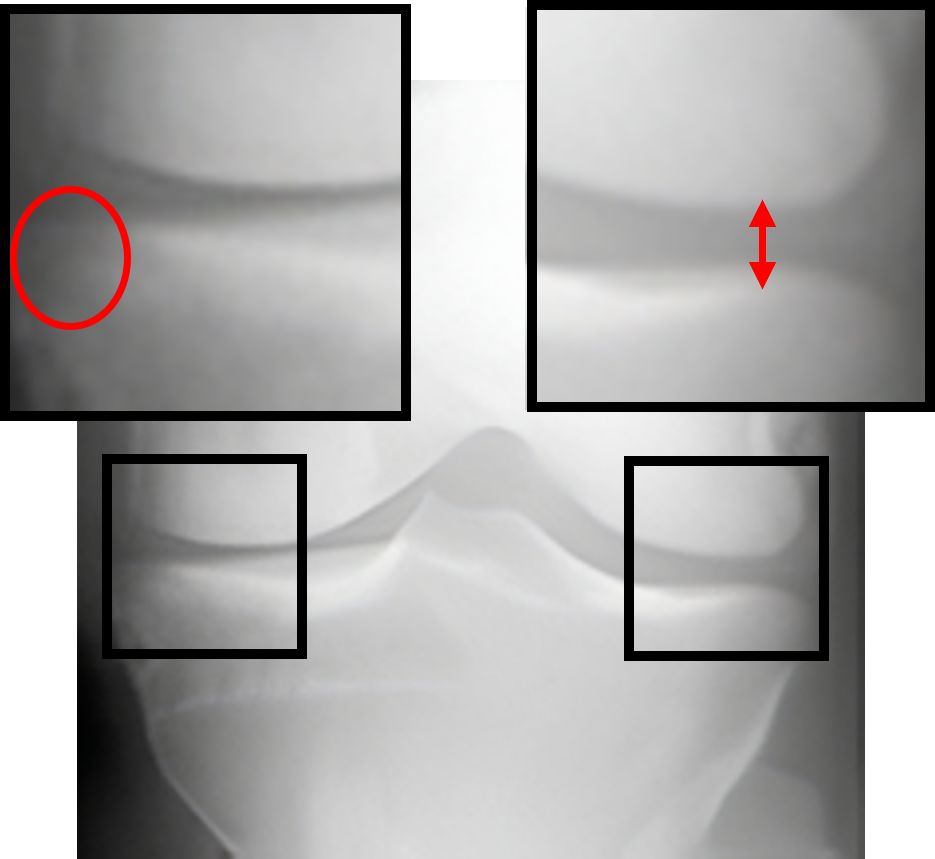

Table 2: Visualization of the synthesized intermediate frames

Input image Synthesized intermediate framessuperscriptSynthesized intermediate frames\stackrel{{\scriptstyle\text{Synthesized intermediate frames}}}{{\makebox[284.52756pt]{\rightarrowfill}}} Input image

xSsubscript𝑥𝑆x_{S} xS(φη=0.25)subscript𝑥𝑆subscript𝜑𝜂0.25x_{S}(\varphi_{\eta=0.25}) xS(φη=0.5)subscript𝑥𝑆subscript𝜑𝜂0.5x_{S}(\varphi_{\eta=0.5}) xS(φη=0.75)subscript𝑥𝑆subscript𝜑𝜂0.75x_{S}(\varphi_{\eta=0.75}) xTsubscript𝑥𝑇x_{T}

KL-0 KL-1∗∗ KL-2∗∗ KL-3∗∗ KL-4

[Uncaptioned image] [Uncaptioned image] [Uncaptioned image] [Uncaptioned image] [Uncaptioned image]

• *

The morphed areas of each frame were highlighted within black boxes, the red arrow and red circle indicate the locations of JSN and osteophyte formation, respectively. A shorter arrow indicates a smaller joint space (i.e., a narrower distance between the tibia and femur), while a larger circle indicates more osteophytes.

• **

The expected labels.

4.2 Visualization of the synthesized intermediate frames

In Table 2, we show the source image xSsubscript𝑥𝑆x_{S}, the target image xTsubscript𝑥𝑇x_{T}, and their intermediate frames (i.e., xS(φη=0.25)subscript𝑥𝑆subscript𝜑𝜂0.25x_{S}(\varphi_{\eta=0.25}), xS(φη=0.5)subscript𝑥𝑆subscript𝜑𝜂0.5x_{S}(\varphi_{\eta=0.5}) and xS(φη=0.75)subscript𝑥𝑆subscript𝜑𝜂0.75x_{S}(\varphi_{\eta=0.75})), which is crucial in understanding how the source images evolve into their registered state. The progressive alignment is quantified by the parameter η𝜂\eta evenly divided into 0.25, 0.5, and 0.75, which represents the extent of transformation at each stage of KOA, corresponding to KL-1, KL-2, and KL-3, respectively. As can be seen, xS(φη=0.25)subscript𝑥𝑆subscript𝜑𝜂0.25x_{S}(\varphi_{\eta=0.25}) shows the initial stage of the morphing process where the morphs are minimal and closely resemble the source image. For xS(φη=0.5)subscript𝑥𝑆subscript𝜑𝜂0.5x_{S}(\varphi_{\eta=0.5}), the morph is more pronounced, introducing clear signs of osteophytes and beginning to show a narrowing of the joint space. It is noteworthy that this frame is critical as it represents the halfway anchor point of the KOA temporal evolution process, showing a balanced mix of characteristics from both the source and target images. xS(φη=0.75)subscript𝑥𝑆subscript𝜑𝜂0.75x_{S}(\varphi_{\eta=0.75}) signifies an advanced stage of morph, introducing moderate multiple osteophytes, definite narrowing of the joint space, some sclerosis, and possible deformity of bone contour.